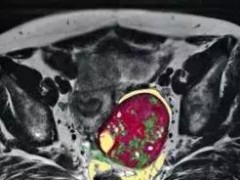

卵巢癌